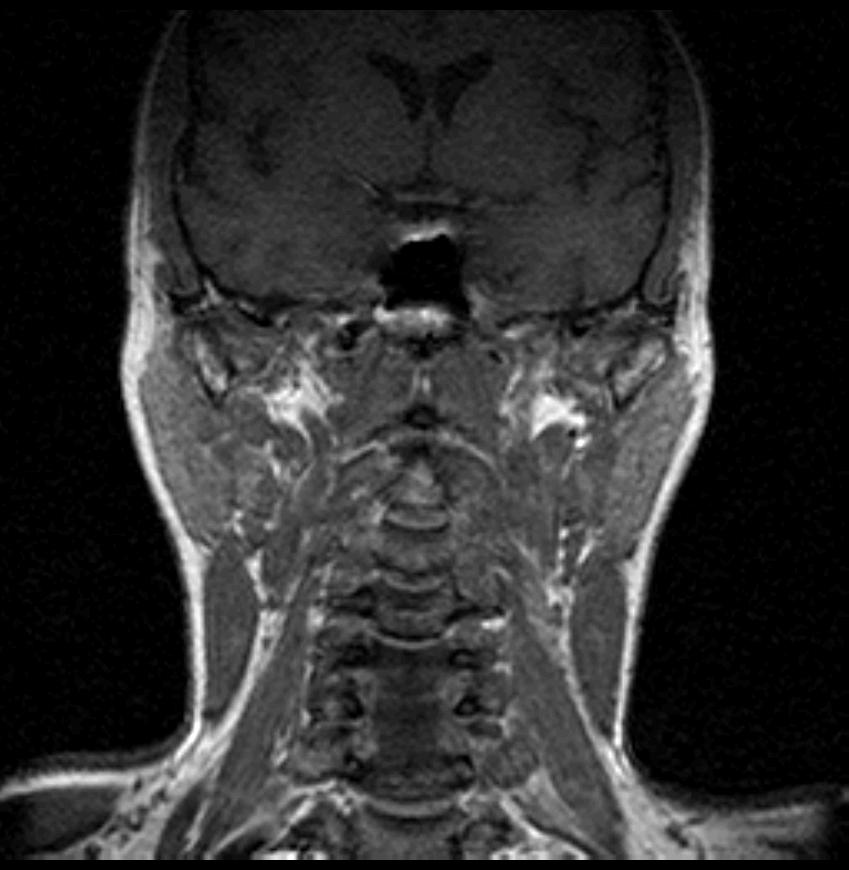

06.06.2011 МРТ - головы и шеи.

Пацентка 36 лет, с жалобами на припухлось в околоушной области справа.

В глубокой доле  правой околоушной железы  на фоне неизмененной паренхимы зона  гетерогенного по Т2, гипоинтенсивного по Т1  с единичными гиперинтенсивными включениями.При контрастировании- накопление контраста диффузное неоднородное и по периферии.Рискну предположить злокачественное образование ( аденокарцинома) с низкой степенью злокачественности( есть капсула, экспансивный рост).Сильно не расстреливайте.

Проблема в том, что перед челюстно-лицевым хирургом стоит распространенность любого объемного процесса, в данном случае все упирается в возмможную травму лицевого нерва и конечно же с дальнейшим его парезом, а ведь женщина  еще молодая. Образование имеет тонкостенную оболочку, по структуре неоднородно, с наличием кальцината, при этом МР-сигнал от окружающих анатомических структур(как костных так и мышечных) не изменен, т.е. об инфильтративном росте речи не идет, в какой то степени доброкачественное. В конкретном случае лицевой нерв с ретромандибулярной веной просто несколько оттеснен.

По гистологии аденома околоушной слюнной железы, но после удаления пока сохраняется парез лицевой мускулатуры, возможно временный.